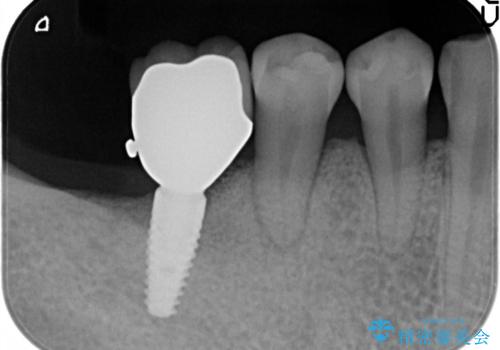

奥歯が痛い。抜歯~奥歯のインプラント

- 奥歯が破折していたため、抜歯を行ったあとインプラントを埋入して咬合回復を行っております。